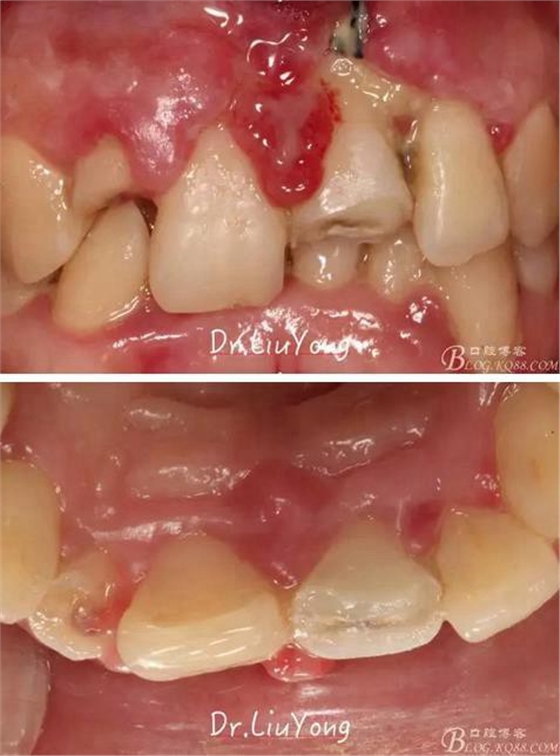

檢查:面部對稱無腫脹畸形,張口度正常,口內(nèi)檢查可見A2牙冠缺失,可見直徑約1.5mm左右穿髓孔,冷熱刺激痛+,叩痛+,探痛+,近中斷面探診位于齦下1.5mm,A1B1B2松動2-3度,B1牙冠缺失1/2,冷熱刺激痛-,叩痛+,B2牙冠完整,A2-B2牙齦紅腫,探診極易出血,全口口腔衛(wèi)生差,牙結石++,A1B1之間牙齦乳頭紅腫嚴重,B1唇側牙齦萎縮明顯,牙齦邊緣可見縫線兩處,局部有滲出,齦緣冠方1mm處見白色骨塊,松動,觸痛明顯,觸及骨塊時可見B1及B2近中唇側牙齦動度,B1B2之間唇側牙齦乳頭缺失,B2近中根面可見大量牙結石。重度深覆合,牙尖交錯位時C3-D2咬至上前牙腭側齦緣,A1切端咬至C12唇側齦緣。其余牙齒未見明顯異常。

術前口內(nèi)照片如下: